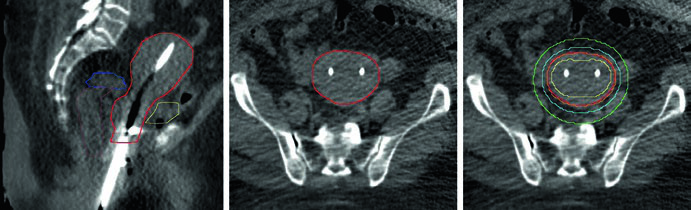

A braquiterapia como parte do tratamento definitivo com preservação de órgão melhora a sobrevida global no câncer vaginal. A radioterapia definitiva é a abordagem preferida para estádio I, com cirurgia como opção apenas em tumores não volumosos distais e não uretrais. Quimiorradioterapia definitiva é preferida para estádios II-IVA.

A braquiterapia intersticial é a abordagem padrão. Somente tumores muito pequenos (espessura ≤5 mm) podem considerar aplicadores intracavitários. O ultrassom transretal guia a colocação de agulhas intersticiais e evita perfuração intestinal. Ao final do procedimento, um toque retal digital confirma que nenhum cateter está perfurando o reto.

Volumes-alvo no câncer vaginal primário

| HRCTV | GTV + margem de 1 cm lateral, inferior e superior |

| IRCTV | HRCTV + extensão microscópica na vagina (inclui toda a doença inicial) |

A dose total alvo deve ser 70-80 Gy, variando conforme a localização vaginal e estruturas adjacentes. Na vagina proximal, 75-80 Gy é aceitável, mas na vagina distal — mais próxima da uretra — deve-se reduzir para 70-75 Gy. Para doença multifocal ou disseminação descontínua, trata-se toda a extensão vaginal para dose equivalente de 60 Gy, com reforço das áreas de tumor residual grosseiro para 70-80 Gy.